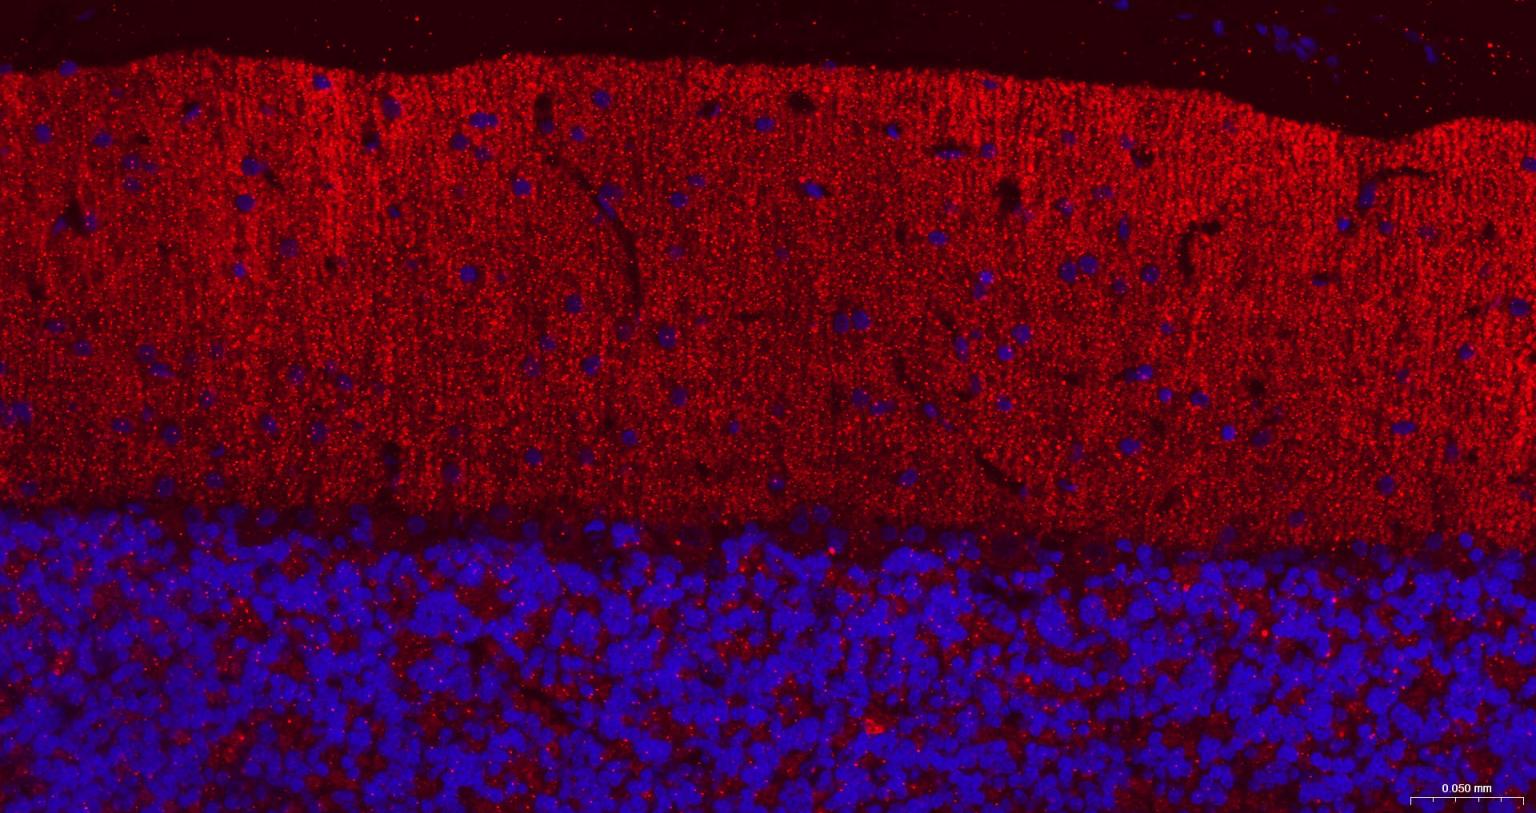

Paraformaldehyde-fixed, paraffin embedded Rat Cerebellum; Antigen retrieval by boiling in sodium citrate buffer (pH6.0) for 15 min; The section was incubated with GABBR2 Monoclonal Antibody, Unconjugated (bsm-54237R) at 1:200 overnight at 4°C. Followed by conjugated Goat Anti-Rabbit IgG antibody (Red, bs-0295G-BF594), DAPI (blue, C02-04002) was used to stain the cell nuclei.